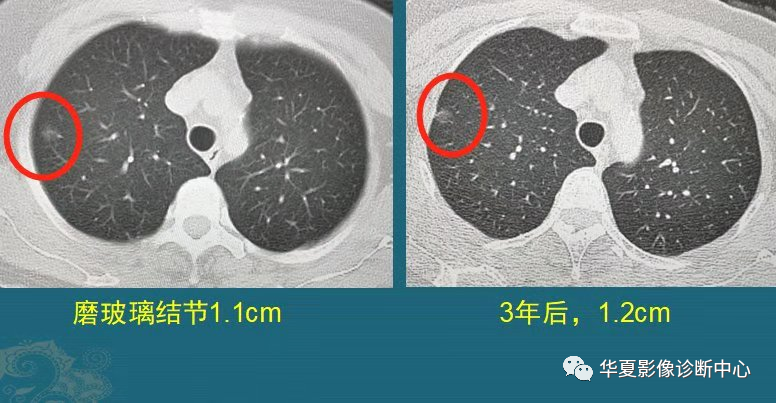

这是一位中年女士,体检发现右肺纯磨玻璃结节1.1cm,定期复查,3年后好像增大了一点,直径大约1.2cm,边缘出现少量细索条影,她不想再观察了,做了胸腔镜微创手术,病理是原位腺癌。